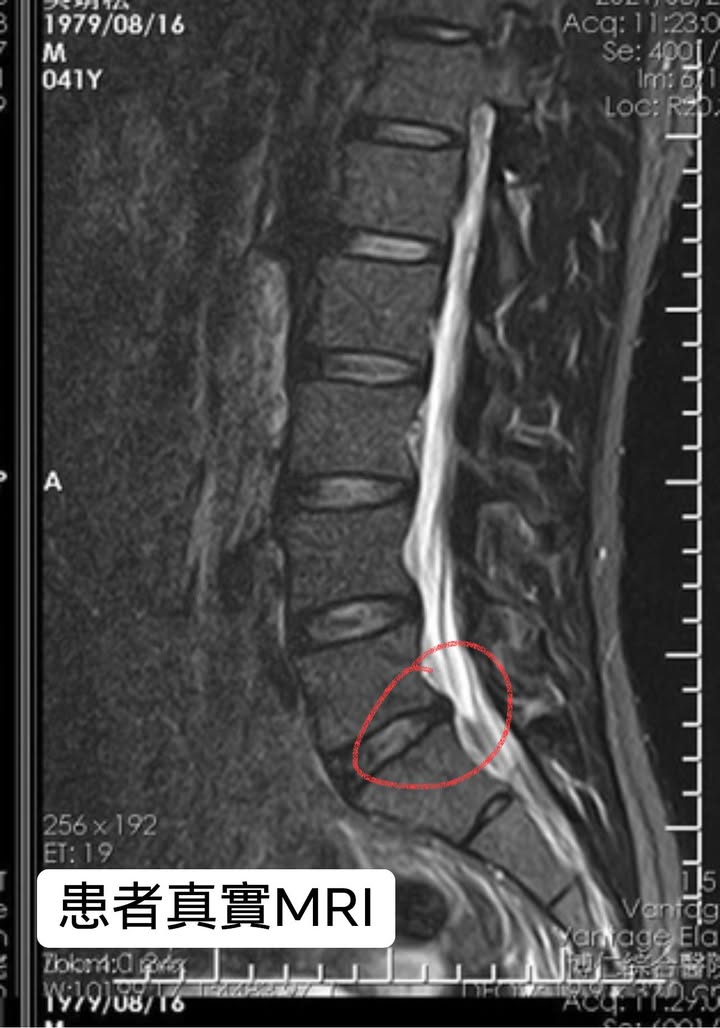

Cervical Spine Treatment Cases 腰椎治療案例 #巨大椎間盤突出醫案 #治療十二次提供前後MRI對比 #縱切面跟橫切面對比 #椎間盤突出為... 2021.09.03 ⭕️今天聽到患者說在某醫學中心開整段脊椎的刀 ,骨釘,骨水泥,人工椎間盤全上了,花... 2021.08.25 #典型下背手術失敗綜合症候群 #頸椎跟腰椎在短短幾年開了三次大刀 #腰椎融合固定支架... 2021.08.17 #馬尾神經症候群特殊醫案 #小便失禁合併下肢無力 #脊椎整合中醫微創逆轉勝 #脊刻救援... 2021.08.13 #骨刺髓核有可能吸收回去嗎?? #疼痛到無法行走的恐怖無法形容 #MRI核磁共振前後對比... 2021.08.14 #巨大椎間盤突出一定要開刀嗎? #兩家醫學中心外科醫師說很嚴重! #有沒有辦法逆轉勝... 2021.08.10 ❖ 椎間盤突出治療醫案 ❖晨起痛爆整個人無法工作心情沮喪 😂骨科醫師說復健如果沒效可... 2022.05.12 #天才年輕賽車手巨大椎間盤突出醫案 #八周治療完全逆轉勝康復 #重新回到合法賽車場競... 2021.07.20 #腰椎滑脫痛苦不堪 #右腳麻痛無法彎腰刷牙 #感謝桃園市楊小姐熱情見證 #患者親自贈送... 2021.06.15 #巨大椎間盤突出醫案 #真的逆轉勝超感動 #三個月治療完全徹底改善 #脊刻救援成功 #徹... 2021.06.12 ⭕️L4L5巨大椎間盤突出治療醫案 🌟八週之內解除危機逆轉成功 😁順利降級成功解封印 💪... 2021.07.08 #腰椎多節椎管狹窄治療醫案 #腎臟病患者可接受中醫微創筋膜療嗎? #感謝台北市信義區張... 2021.06.01 #腰椎手術失敗綜合症候群 #感謝桃園呂伯伯熱情見證 #何時必須優先考慮再次動刀 #脊刻... 2021.07.31 #感謝新店吳先生熱情見證 #車禍後導致椎間盤突出醫案 #傳統復健六周無效痛苦不堪 #脊... 2021.05.29 #椎間盤突出治療醫案 #破紀錄三週解決 #真的逆轉勝 #感謝新莊周先生熱情見證 #脊椎整... 2021.05.26 ← 上一頁 6 7 8 9 10 下一頁 →